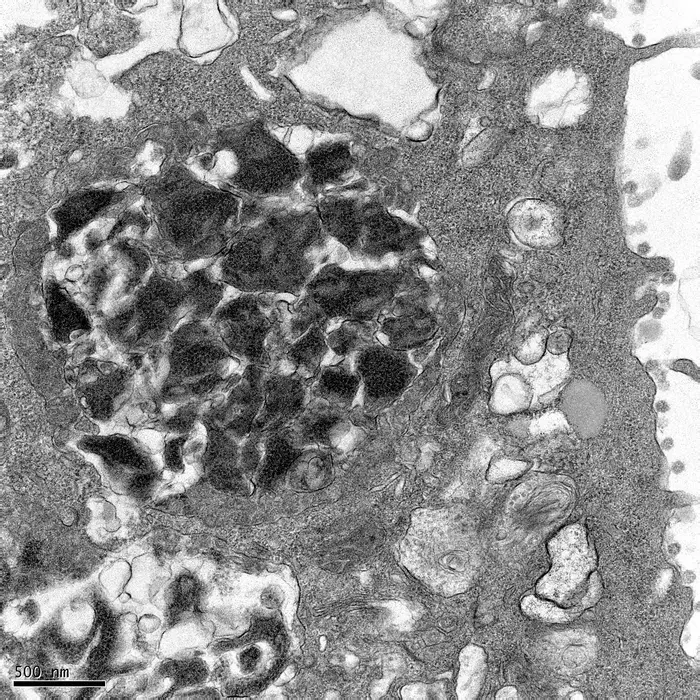

This transmission electron microscopy image shows 3a dense bodies (3DBs), the darkest parts of the image, inside a cell infected with SARS-CoV-2. 3DBs play a critical role regulating the processing of the virus’s spike protein, before the spike protein is assembled into complete viral particles.

view moreCredit: Jueqi Chen/University of Chicago

Specifically, SARS-CoV-2 ORF3a appears to play a vital role in protecting structural proteins, most notably the spike protein that facilitates spread into other cells, as they are assembled on the surface of viral particles. It does this by driving the formation of a dense group of proteins that surround the spike protein and provide protection while in transit, much like security detail protecting a person or an armored vehicle carrying cash to the bank.

The team in Chicago, led by Assistant Professor Jueqi Chen, Ph.D., termed these protective complexes “3a dense bodies” or 3DBs for short.

It appears that 3DBs help prevent the spike protein from being cut into smaller components. When ORF3a is missing, these 3DBs fail to form, and the spike protein often arrives damaged, severely impairing the nascent virus’s ability to infect new cells.